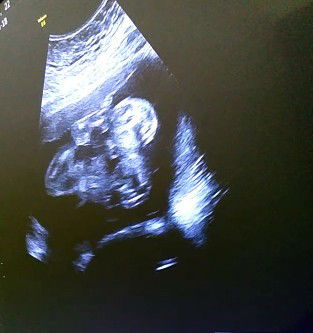

Bayi sungsang

Bun boleh nanya gak? Gimana ya caranya Mengatasi bayi sungsang.